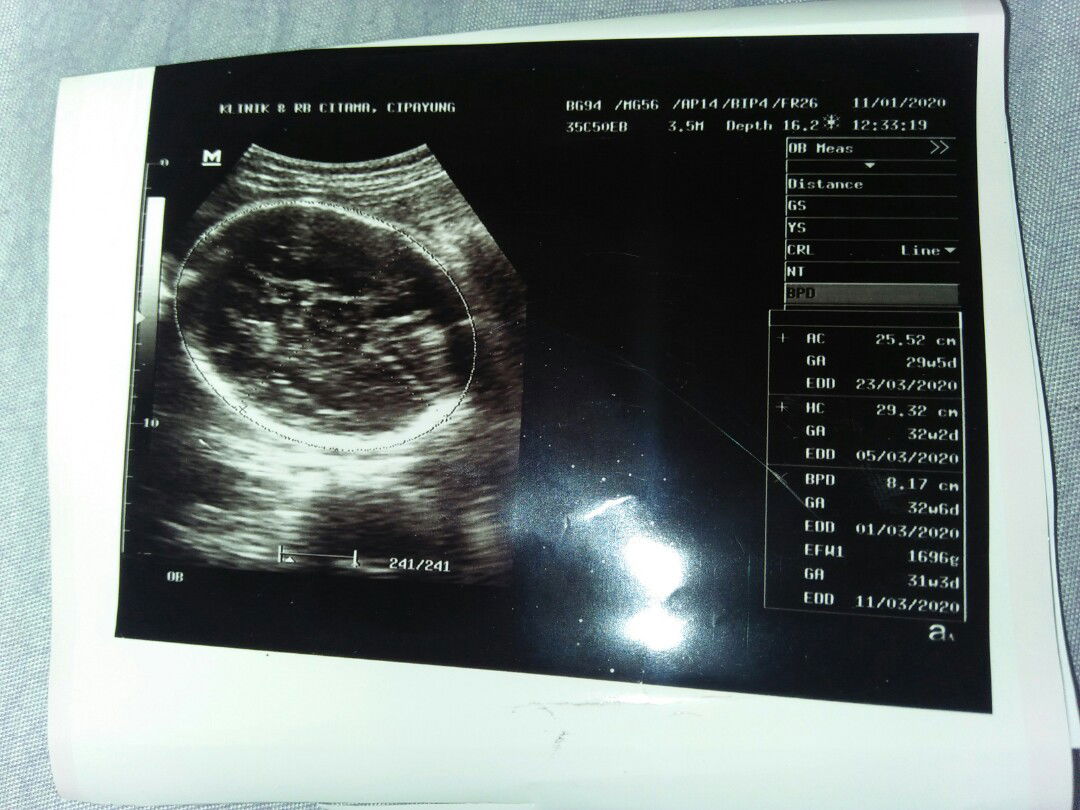

Ada yg tau ga bun kira2 itu brapa week ya.-.-

Lihat GAnya bun